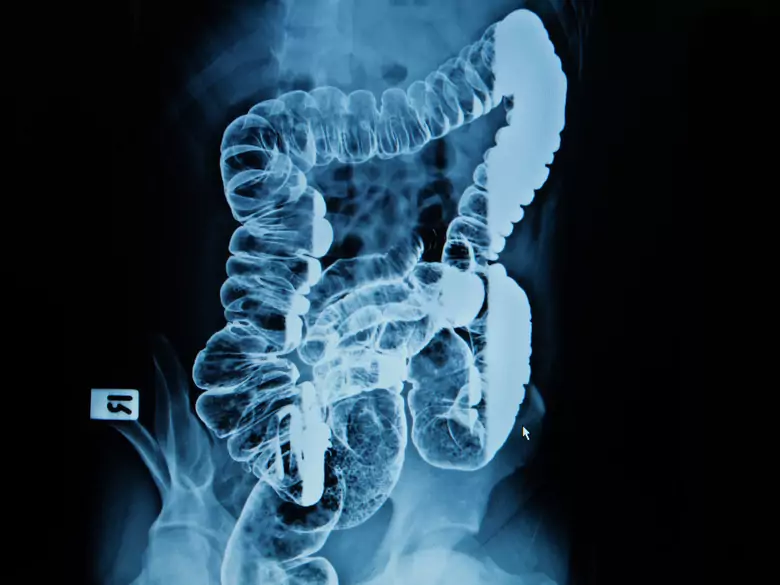

Colorectal cancer - causes, symptoms, diagnosis, treatment

Bowel examination